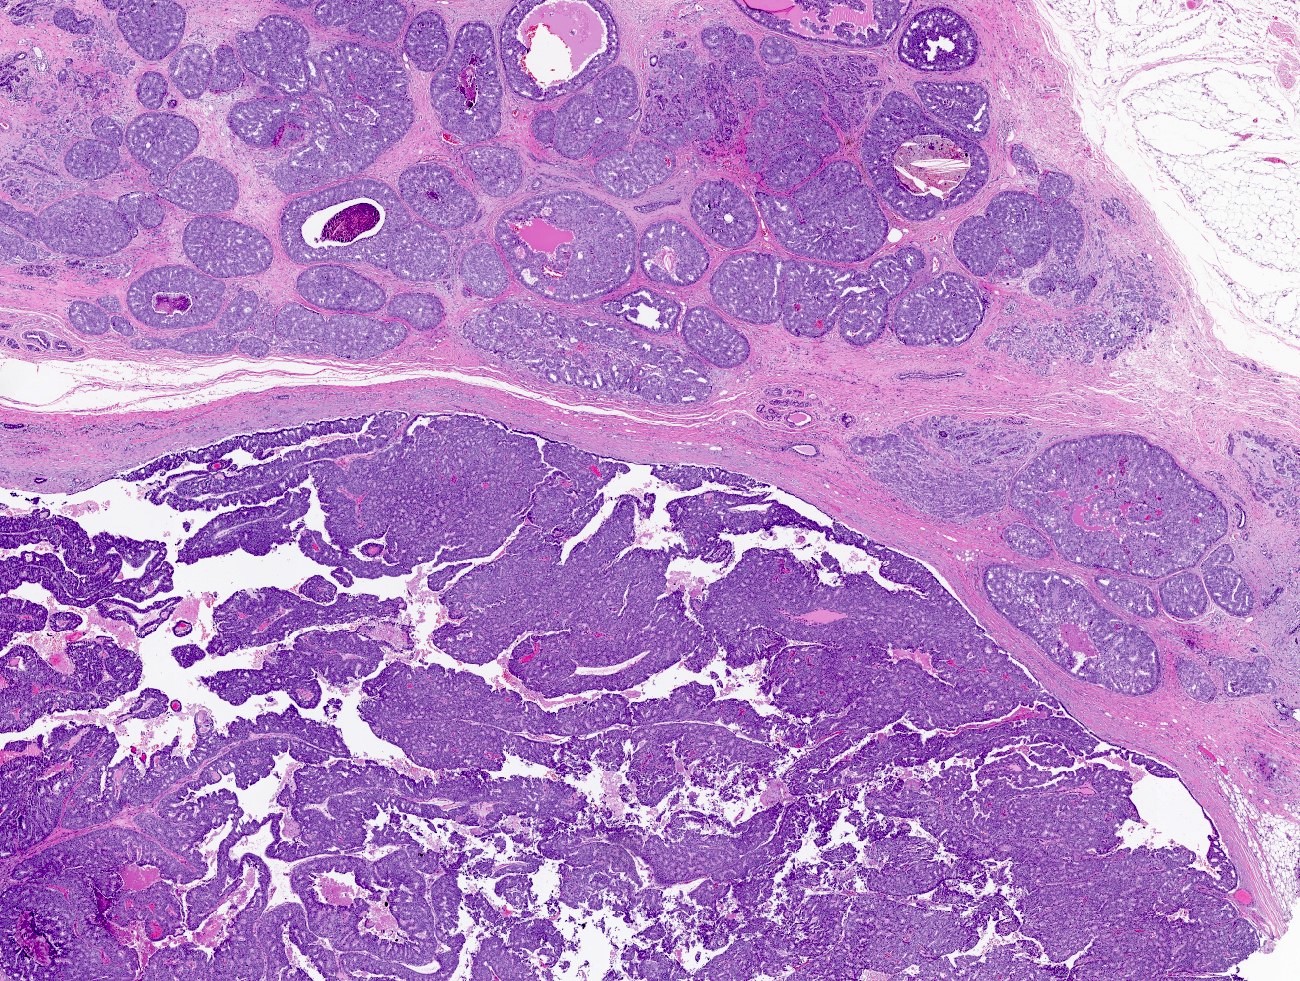

- Papillary tumor with pushing borders, may be within a cystically dilated duct, surrounded by a thick fibrous capsule (Histopathology 2008;52:20, Mod Pathol 2021;34:1044, Virchows Arch 2022;480:5)

- Delicate papillary fronds with fibrovascular cores lined by cuboidal to columnar epithelial cells with low to intermediate grade atypia

- Cribriform and solid architecture may be present

- Most show complete lack of myoepithelial cells along the papillae and around the periphery of the tumor (Am J Surg Pathol 2006;30:1002, Am J Surg Pathol 2011;35:1)

- Invasive carcinoma is defined as the presence of neoplastic cells infiltrating beyond fibrous capsule (Mod Pathol 2021;34:1044)

- Most commonly invasive carcinoma of no special type (IDC NST), small (pT1), ER+, HER2- and low grade (Am J Surg Pathol 2011;35:1093, Breast J 2021;27:209, Breast J 2019;25:539, Curr Probl Cancer 2018;42:291)

- Staging is based on the size of the conventional invasive component if present

- Epithelial displacement / entrapment of neoplastic cells within capsule can occur and must be distinguished from true invasion beyond the fibrous capsule

Microscopic (histologic) images

Contributed by Kristen E. Muller, D.O. , Mariel Molina Nunez, M.D. and Julie Jorns, M.D. (Case #518)